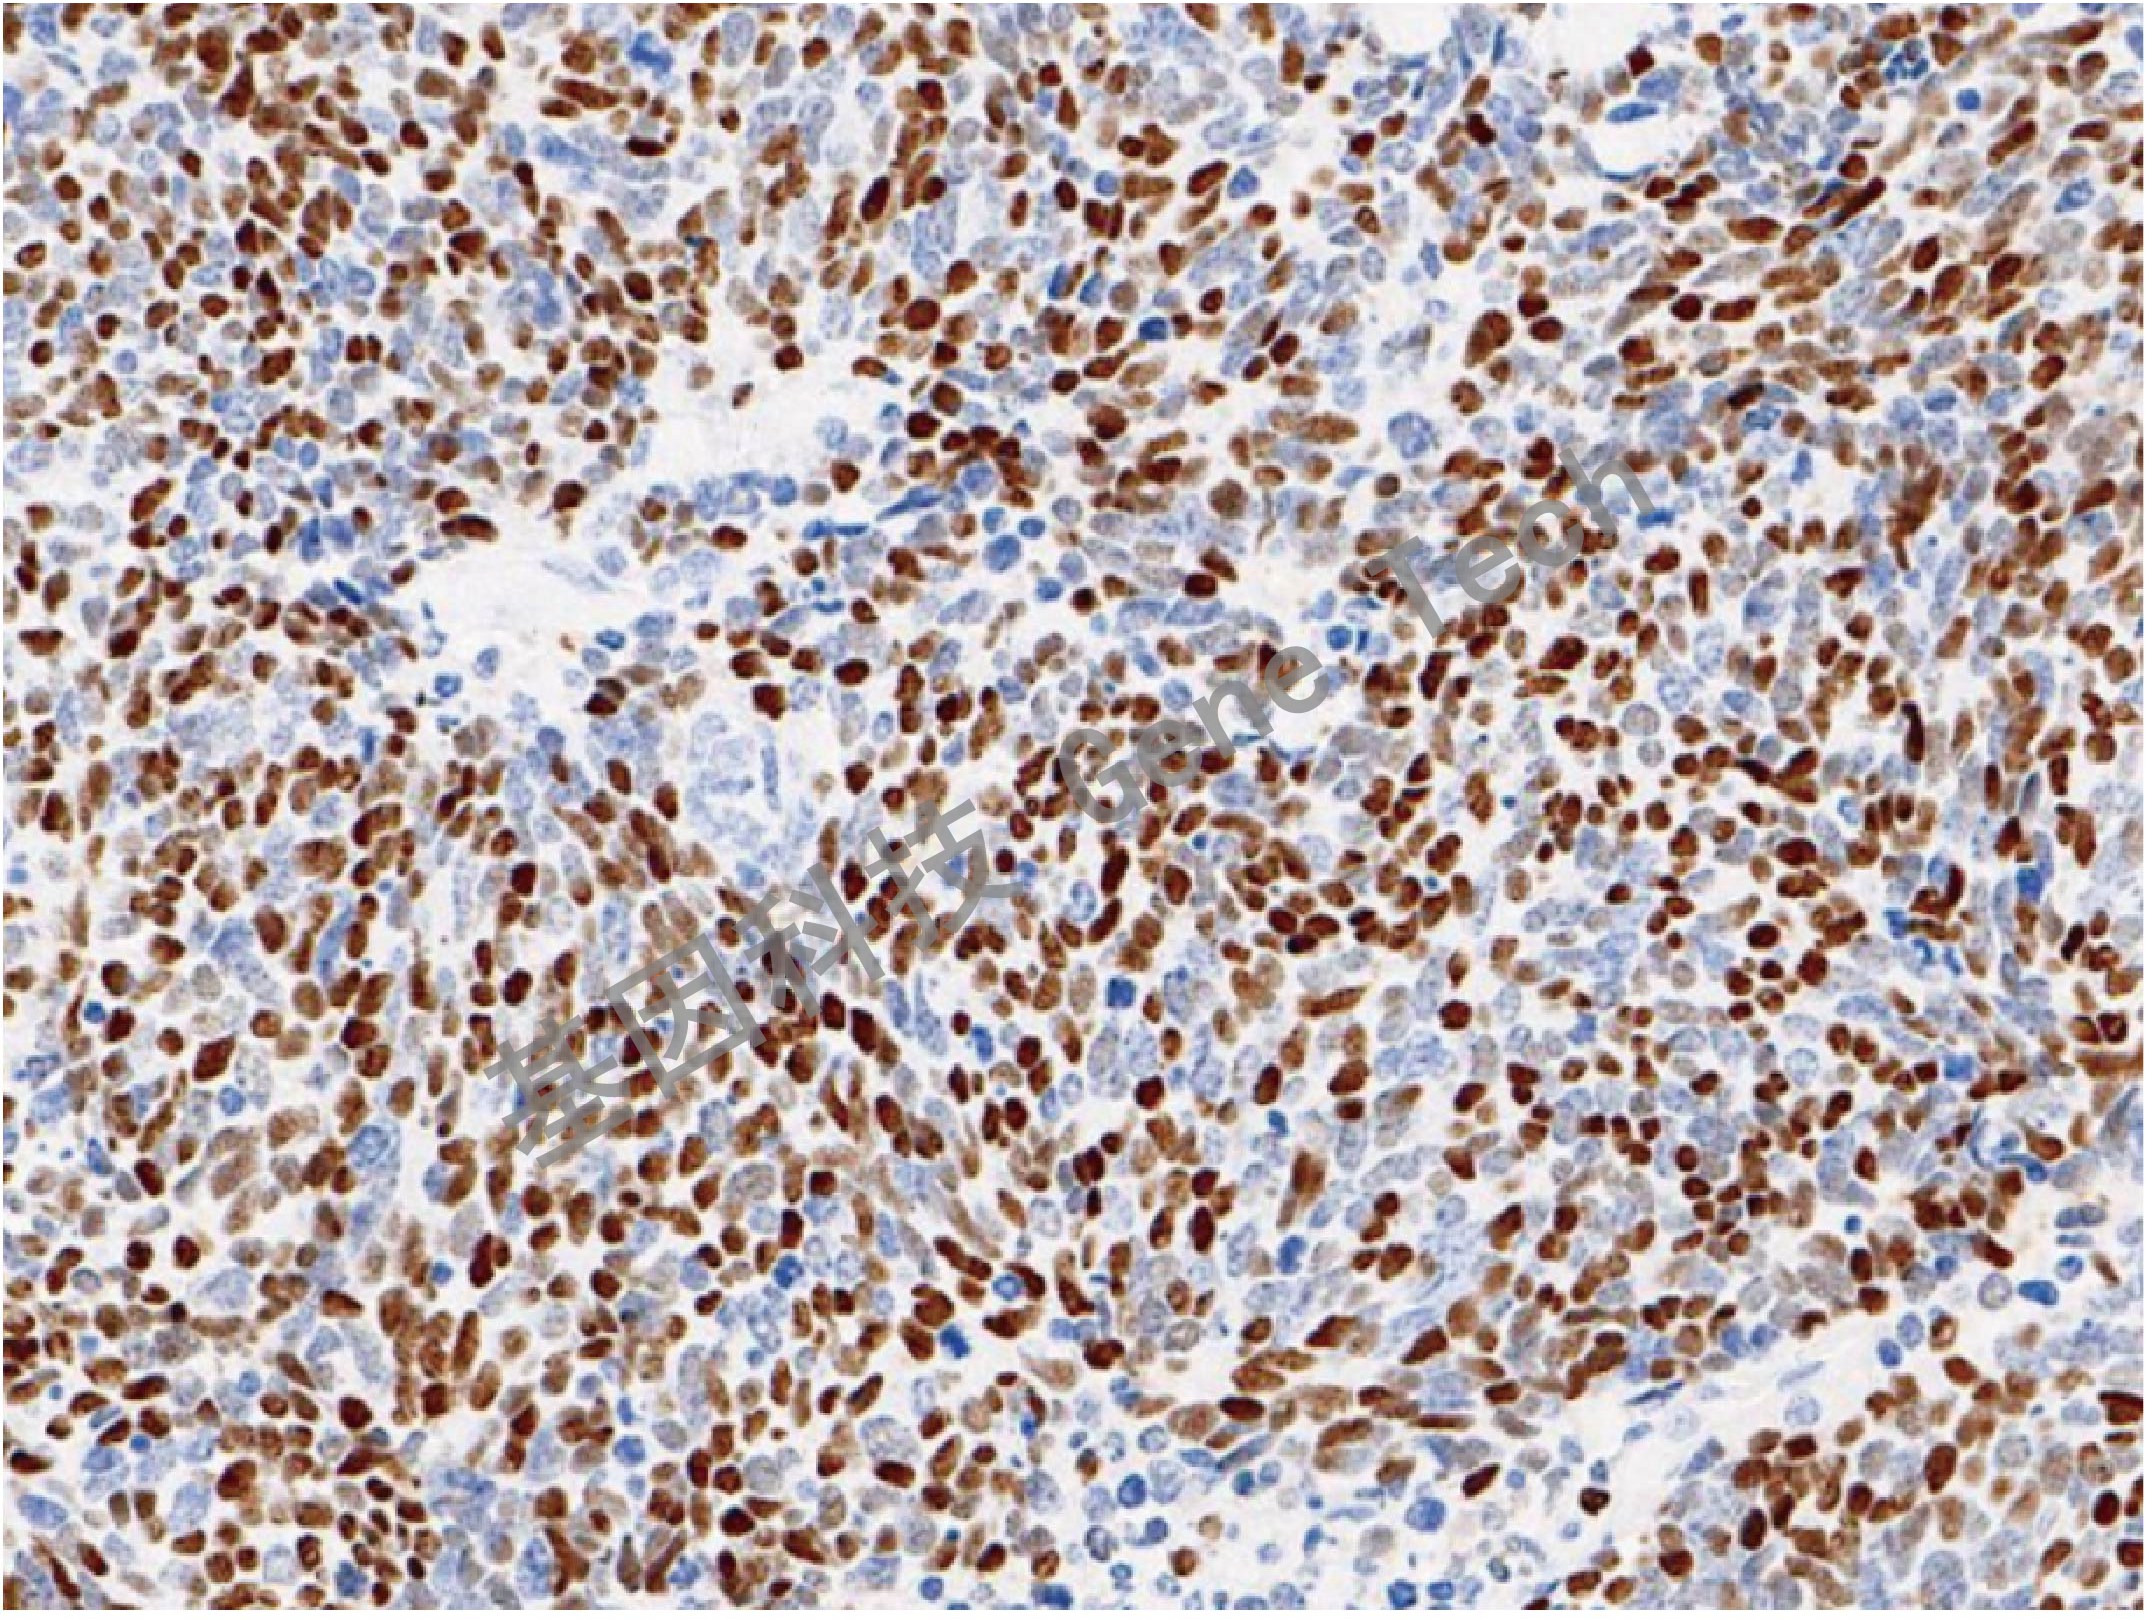

MCC 鼠抗人 肥大細(xì)胞類凝乳蛋白酶(MCC)抗體試劑(免疫組織化學(xué)法)

| 克隆號(hào):CC1 | 種屬:鼠 | 適用染色系統(tǒng):GTvisionTM |

| 預(yù)處理:高pH熱修復(fù) | 陽性部位:細(xì)胞膜 | 陽性對(duì)照:扁桃體/闌尾 |

| 簡(jiǎn)介:MCC(Mast Cell Chymase, 肥大細(xì)胞類凝乳蛋白酶)是肥大細(xì)胞的重要標(biāo)志,是肥大細(xì)胞分泌的主要蛋白酶之一,也是重要的炎癥介質(zhì)。用于研究肥大細(xì)胞在皮膚、滑膜、肺和心臟中的分布以及肥大細(xì)胞參與的相關(guān)疾病的診斷治療的研究。 | ||

| 闌尾石蠟切片,用 MCC(GT2431)染色,細(xì)胞膜陽性,DAB 顯色。 | ||